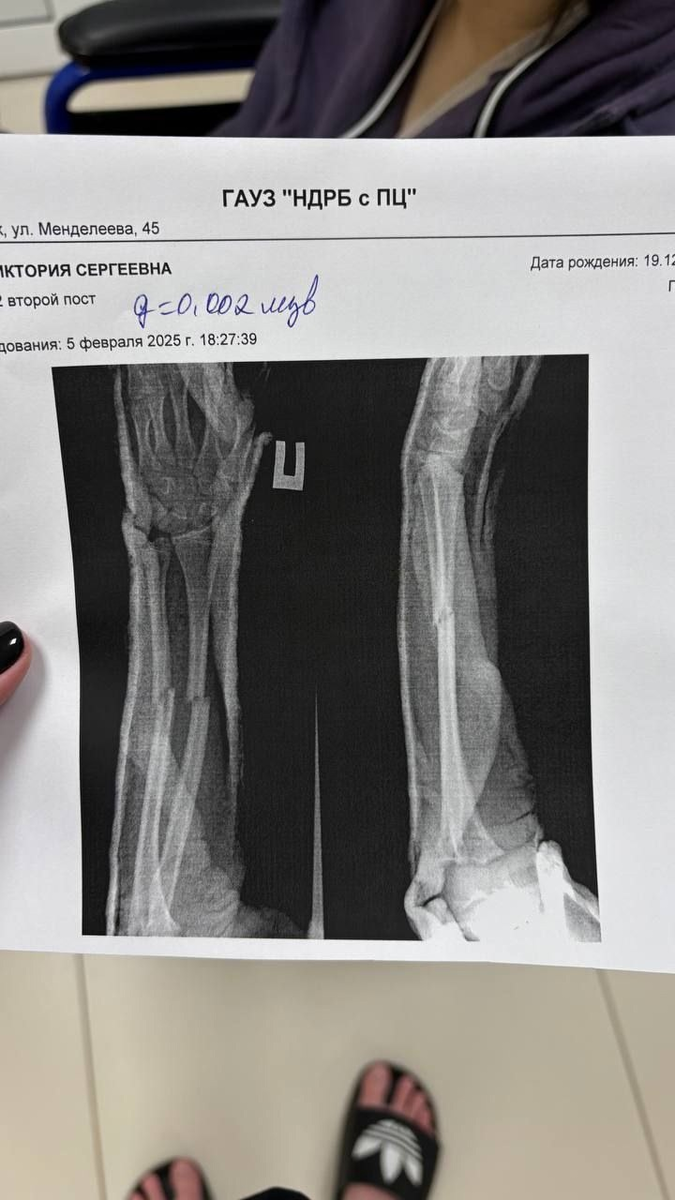

Школьница не стала спорить и попыталась уйти, но ее схватили за руку и с силой бросили на пол. В результате – закрытый перелом обеих рук и экстренная госпитализация.